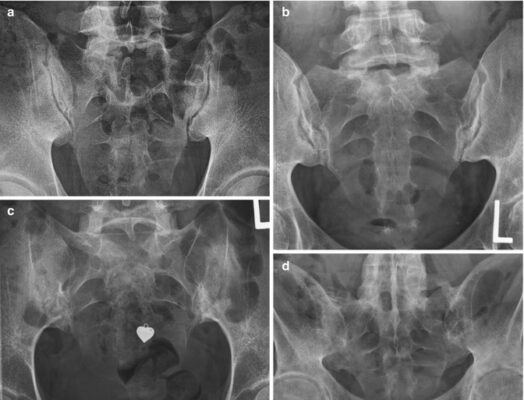

Phân loại trên X quang khớp cùng chậu:

| Độ | Mô tả | Đặc Điểm X-quang Chính | Ý Nghĩa |

| 0 | Bình thường | Khớp cùng chậu bình thường, bờ khớp rõ, khe khớp đều. | Không có VKCC trên X-quang. |

| 1 | Nghi ngờ | Thay đổi nhỏ, nghi ngờ, không rõ ràng, có thể bờ khớp không nét hoặc khe khớp hơi không đều nhẹ. | Nghi ngờ VKCC, cần theo dõi thêm và xem xét các yếu tố lâm sàng khác. |

| 2 | VKCC tối thiểu | Dấu hiệu VKCC nhẹ, ăn mòn và xơ hóa nhẹ bắt đầu xuất hiện, khe khớp có thể hẹp nhẹ. | VKCC mức độ nhẹ, có thể đủ tiêu chuẩn chẩn đoán VCSTD khớp nếu kết hợp với các tiêu chuẩn lâm sàng (theo Tiêu Chuẩn New York Cải Tiến). |

| 3 | VKCC rõ rệt | VKCC tiến triển, ăn mòn khớp, xơ hóa, hẹp khe khớp rõ ràng, đặc xương dưới sụn, ổ khuyết xương. | VKCC mức độ trung bình đến nặng, thường đủ tiêu chuẩn chẩn đoán VCSTD khớp theo Tiêu Chuẩn New York Cải Tiến. |

| 4 | VKCC dính khớp | Dính khớp hoàn toàn hoặc gần hoàn toàn, khe khớp biến mất, xương cùng và xương chậu dính liền. | VKCC giai đoạn muộn, dính khớp, thường là hậu quả của VCSTD khớp kéo dài và không được điều trị hoặc điều trị không hiệu quả. |

Minh hoạ:

Kết luận với Chụp X quang thường quy: Trong những thập kỷ qua, tiến bộ đáng kể trong lĩnh vực hình ảnh học ở Viêm đốt sống thể trục (axSpA) đã cung cấp các kỹ thuật khác nhau để chẩn đoán, phân loại, đánh giá hoạt động của bệnh, tổn thương cấu trúc và tiên lượng cho bệnh nhân mắc axSpA. Tuy nhiên, tiêu chuẩn vàng để đánh giá tổn thương cấu trúc ở bệnh nhân mắc axSpA là X quang. Những thay đổi viêm hoạt động, không được phát hiện bằng XQ hoặc chụp cắt lớp vi tính (CT), được phát hiện tốt nhất bằng MRI.